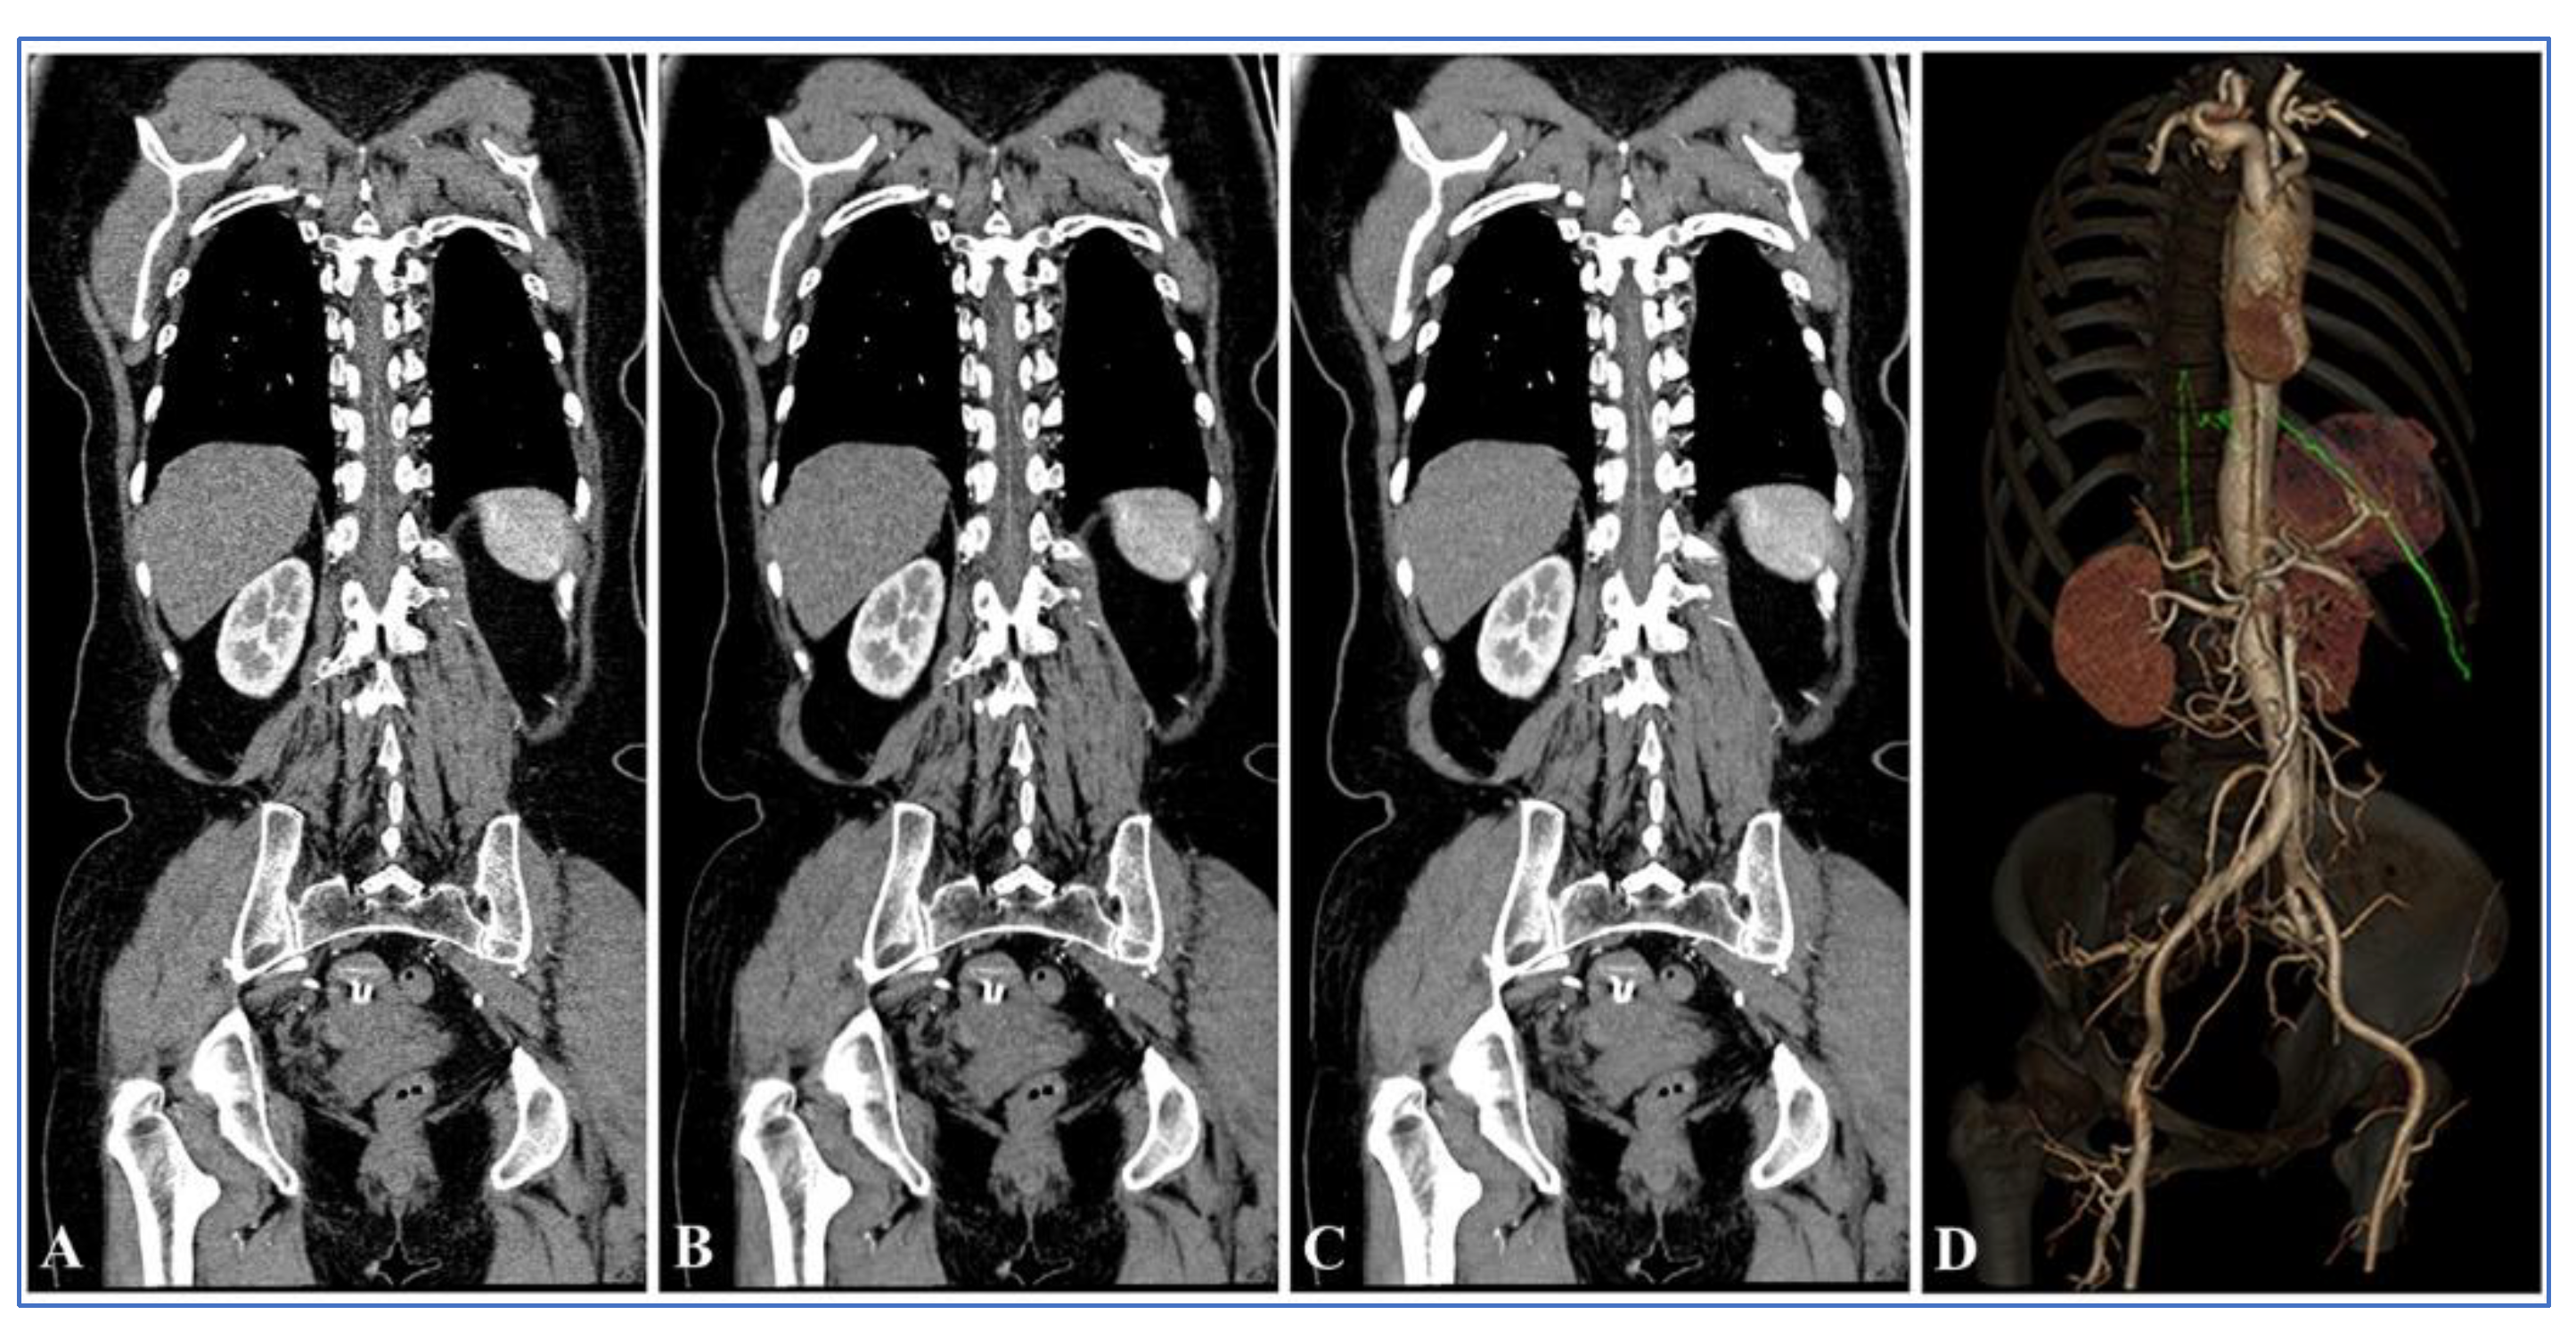

3.4. Visual Analysis of the AKA